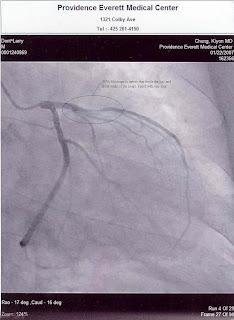

(Ava mindlessly waits on Mom's back with a sucker given by another patient during Grandpa's cath scan and stint procedure)